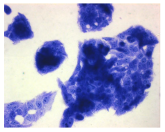

| Control | Doxycycline (DOX) | DOX + C1 | DOX + C2 | |

|---|---|---|---|---|

| SH-SY5Y cells | ||||

| May–Grunwald staining | ![]() | ![]() | ![]() | ![]() |

| HepG2 cells | ||||

| HEK-293 cells | ||||